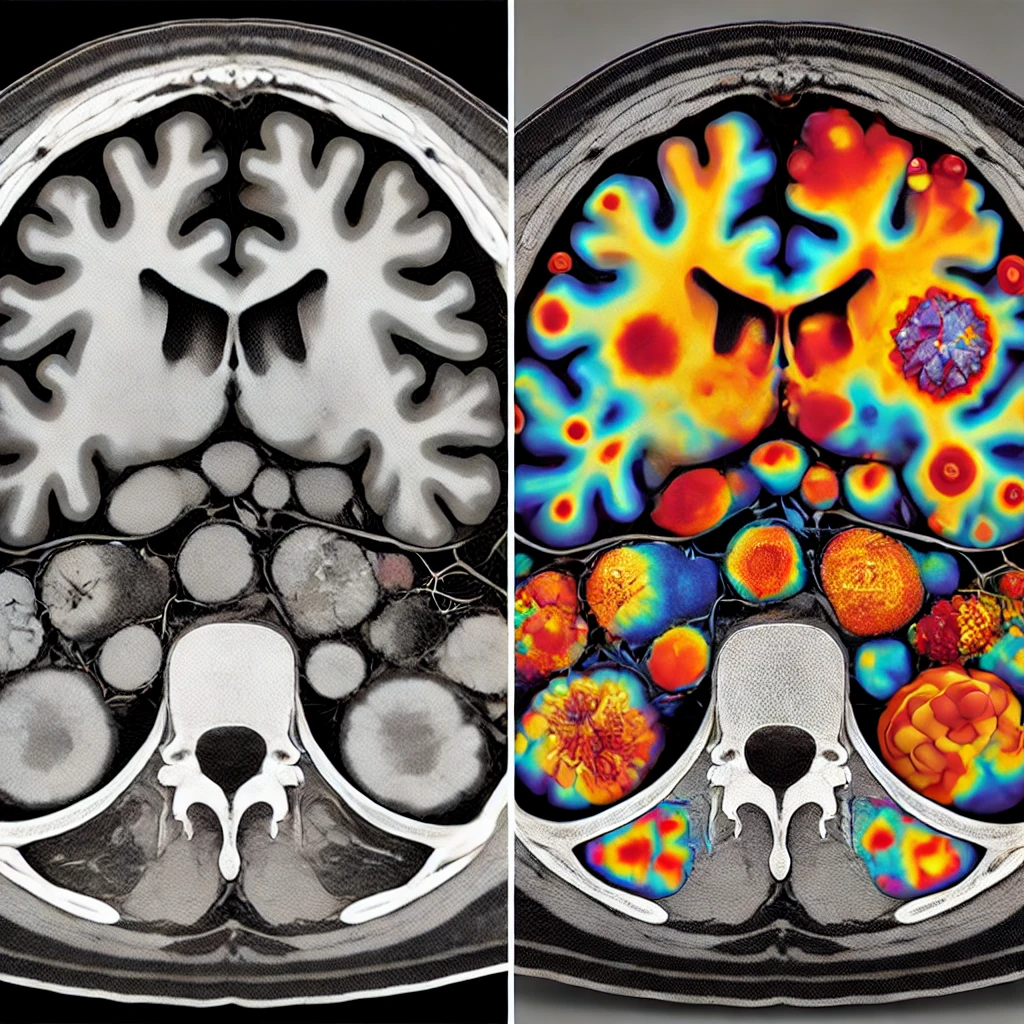

CT 스캔은 전산화단층촬영(CT: Computed Tomography)

다양한 위치에서 여러 개의 X선(X-ray) 빔을 사용하여 신체 내부 구조(골격, 장기, 혈관 등)를 조직의 밀도 차이를 기반으로 자세한 이미지로 구현합니다. X선과 마찬가지로 CT는 저선량 이온화 방사선에 노출됩니다.

PET-CT 스캔이란?

PET 스캔은 방사성 동위원소를 이용해 신진 대사(종양세포 유무, 암세포 활동성 평가, 심혈관 질환, 신경계 질환)가 일어나는 신체가 정상적 기능을 하는지 세포에서 일어나는 화학적 과정의 변화를 시각화하고 측정하는 의료 영상 기술입니다.

| 스캔 영상자료를 통해 얻을 수 있는 정보 | 해부학적 구조적 정보 | 장기 내 구조와 대사과정의 정보 |

| 해상도 | 조직의 밀도차이를 기반으로 구조를 시각화, 높은 해상도로 세밀한 구조 확인가능 |

방사성 동위원소를 주입해 대사 활동이 일어나는 부위가 이를 흡수하고 방사선을 방출하는 것을 시각화함, 기능적 정보제공에 초점이 맞춰져 CT보다 해상도가 떨어집 |

| 사용목적 | 해부학 구조적 이상을 탐지 | 세포의 대사 및 활동성을 확인 |